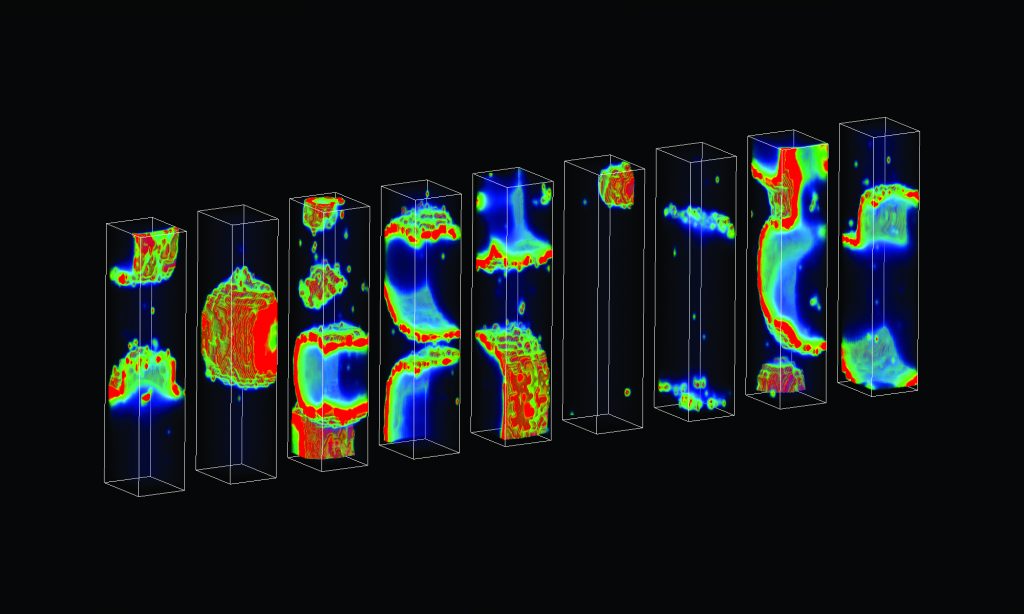

New Study Uncovers Major Cause Of Deadly Heart Arrhythmias | Hub

hub.jhu.eduNew study uncovers major cause of deadly heart arrhythmias | Hub

hub.jhu.eduNew study uncovers major cause of deadly heart arrhythmias | Hub

Finding The Rhythm Of Sudden Cardiac Death | Circulation Research

www.ahajournals.orgFinding the Rhythm of Sudden Cardiac Death | Circulation Research

www.ahajournals.orgFinding the Rhythm of Sudden Cardiac Death | Circulation Research

Averting Deadly Arrhythmias - JHU Engineering Magazine

engineering.jhu.eduAverting Deadly Arrhythmias - JHU Engineering Magazine

engineering.jhu.eduAverting Deadly Arrhythmias - JHU Engineering Magazine